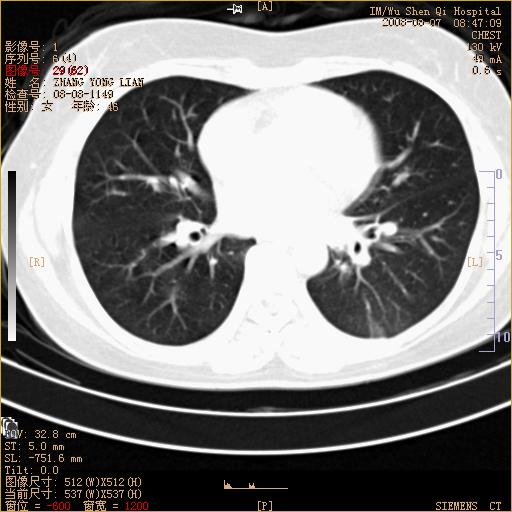

标题: CT15050:女,46岁,咳嗽胸痛一月余 [打印本页]

标题: CT15050:女,46岁,咳嗽胸痛一月余

纵隔窗没发全,左下肺近胸膜处结节。有长毛刺,纵隔淋巴结增大,不排除恶性病变。

考虑左肺下叶后基底段周围型肺癌伴纵隔淋巴结转移可能性大。

左下肺ca并纵隔及左肺门区淋巴结转移。

1)考虑左肺下叶后基底段周围型肺癌伴纵隔淋巴结转移。2)脾内低密度灶,性质待定;不排除转移瘤可能。

考虑左肺下叶后基底段周围型肺癌伴纵隔及肺门淋巴转移。